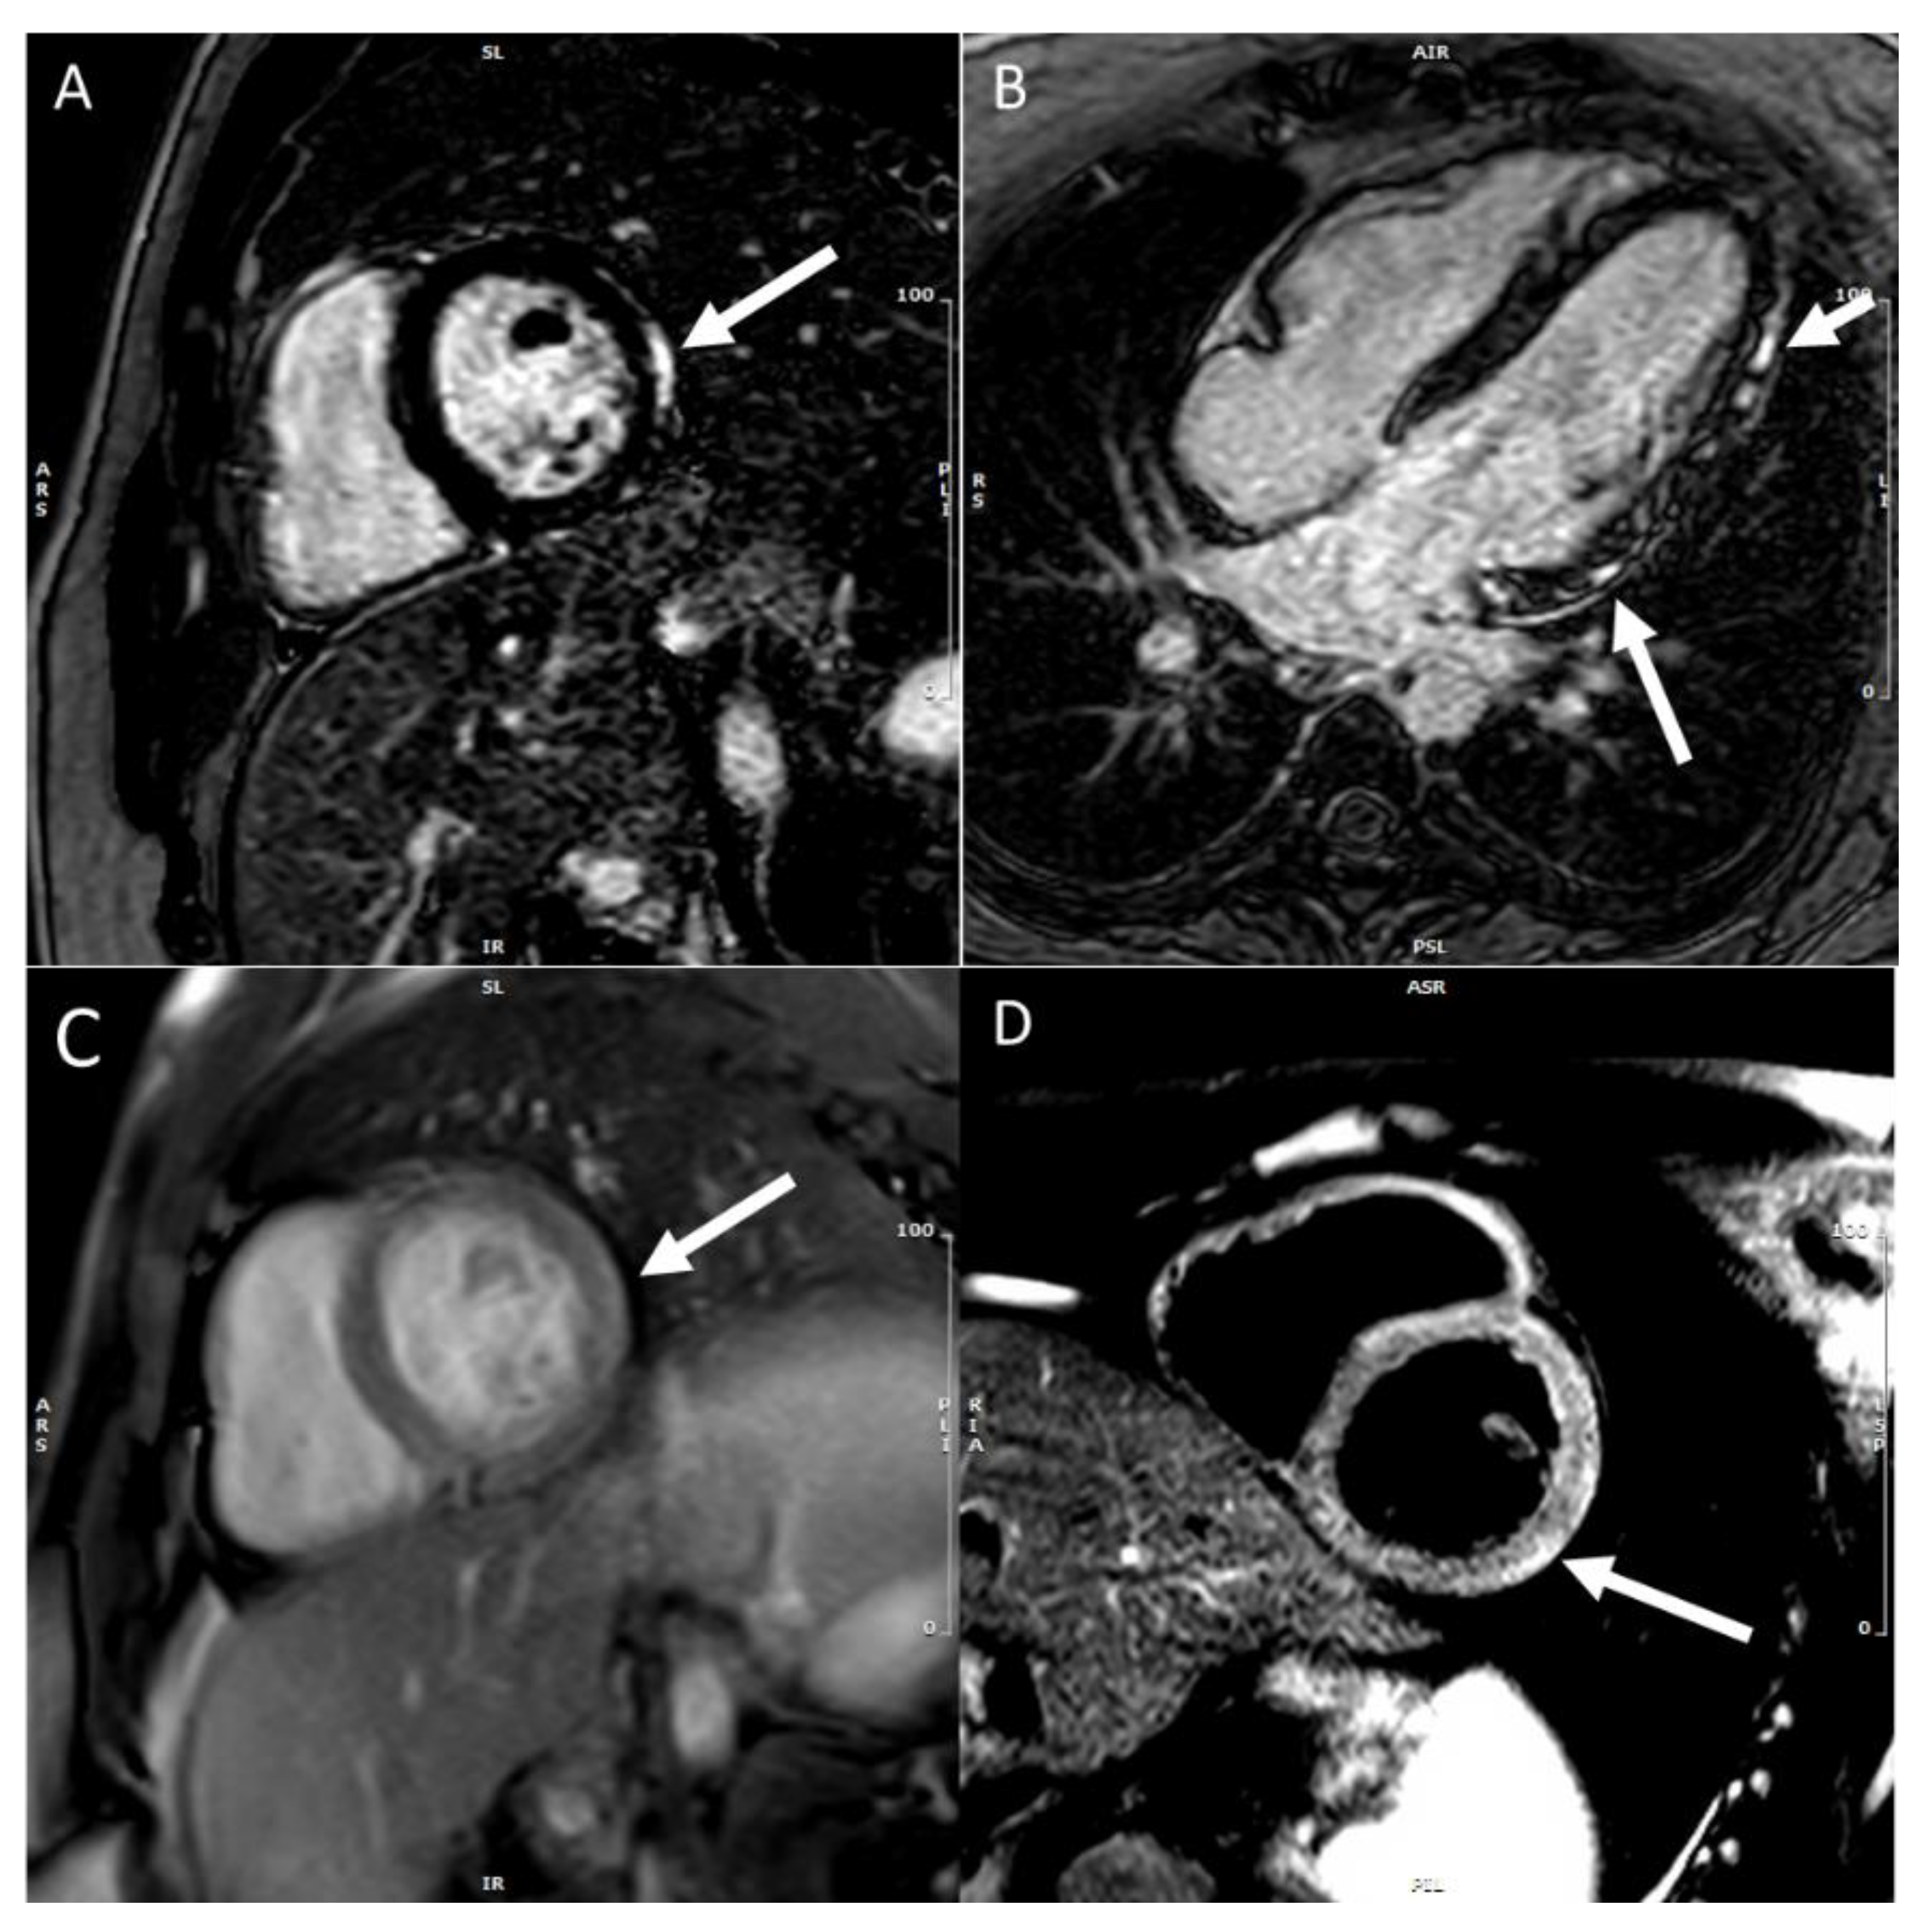

5. CMR in COVID-19-Associated Myocarditis

6. CMR in Myocarditis with MIS-C

7. CMR in mRNA COVID-19 Vaccine-Associated Myocarditis